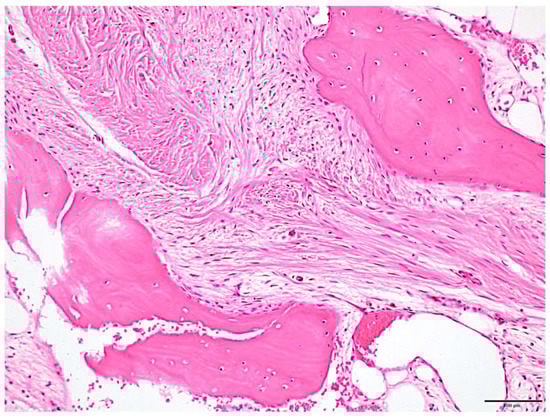

2. Case Presentation